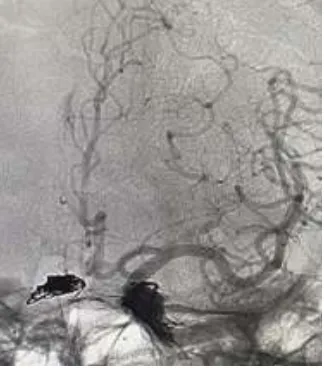

A digital subtraction angiography (DSA) was performed that revealed a Type D CCF with an early filing of the right cavernous sinus in the arterial phase. Based on the rapidly deteriorating clinical picture, shunt anatomy, and hemodynamics a decision was taken to symbolize the CCF.

DSA cerebral angiogram revealing a CCF with an early filling of the right cavernous sinus in the arterial phase.

The patient was placed supine on the angiographic table. The patient was intubated, and the procedure was performed under general anesthesia following strict aseptic protocol, and simultaneous right transfemoral venous and left transfemoral arterial access was taken. A 5F diagnostic catheter from the left groin puncture was placed at the common carotid artery and was navigated from the right transvenous groin access through the inferior vena cava, right atrium, superior vena cava, and the jugular vein. At the level of the jugular sigmoid junction, a microcatheter was maneuvered into the inferior petrosal sinus(IPS) leading to the CS. After cannulating the CS, an angiogram was performed to confirm the position of the microcatheter. Embolization was done with Onyx on the left side and coils on the right side of the CS.

DSA cerebral angiogram showing the placement of coils on the right side and Onyx embolization on the left side.

The final angiogram demonstrated occlusion of the CCF with arterial branches within the normal limits. The procedure was completed, and the patient was extubated without any new neurological deficit. A total of five coils and 2ml of Onyx were used to achieve complete embolization

The final check angiogram demonstrating occlusion of the CCF with the normal arterial flow.